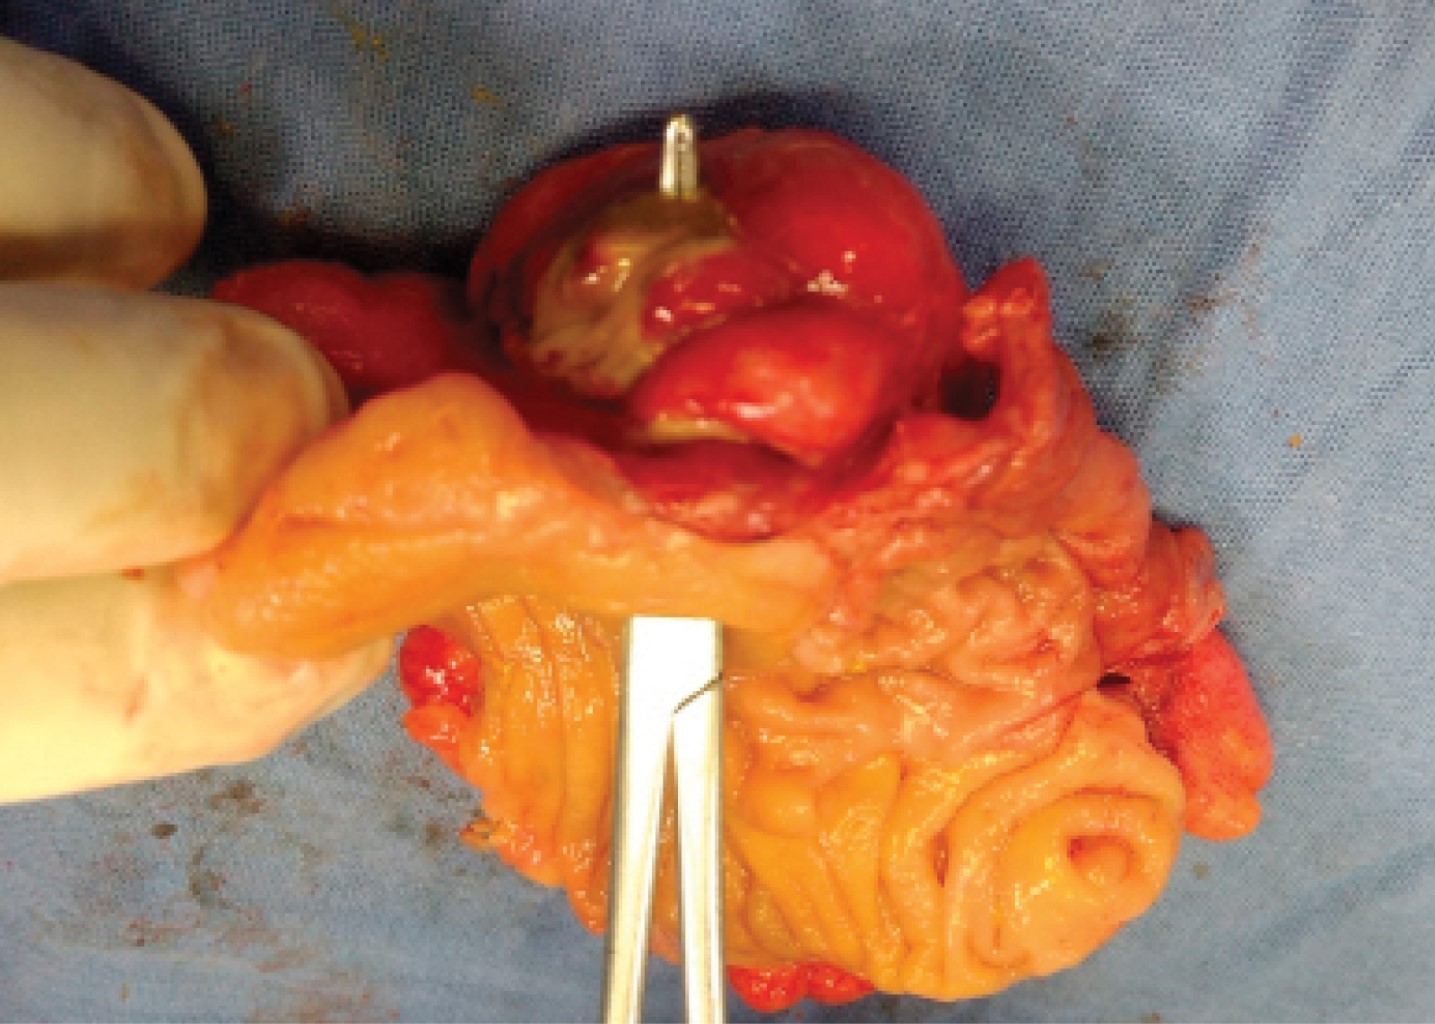

A clinical diagnosis of complicated appendicitis was made and the patient programmed for an appendectomy. A Mcburney's incision was made, a slightly edematous cecal appendix was observed, with a small fecalith inside. An appendectomy was performed, with ligation of the mesoappendix and the appendix base, section, and extraction. On the junction of the cecum with the ascending colon at the antimesenteric border, a plastron was found. Upon pressure the affected area discharged pus. Resection of the affected segment (cecum and a segment of 5 cm of distal ileum) was decided, with the closure of the distal end with Hartmann's technique (two planes of polyglactin 910) and a terminal ileostomy. The segment corresponded to a perforated cecum diverticulum classified as Hinchey II-III (Figure 1).

The pathology report confirmed a 1 × 0.5 cm diverticulum with lymphocytic infiltration and polymorphonuclears, macrophages, and fibrin (diverticulitis) (Figures 2 and 3). The appendix report showed no evidence of pathology (lymphoid follicles, germinal nodes with macrophages, and submucosa with loosely vascularized connective tissue).

Figure 1